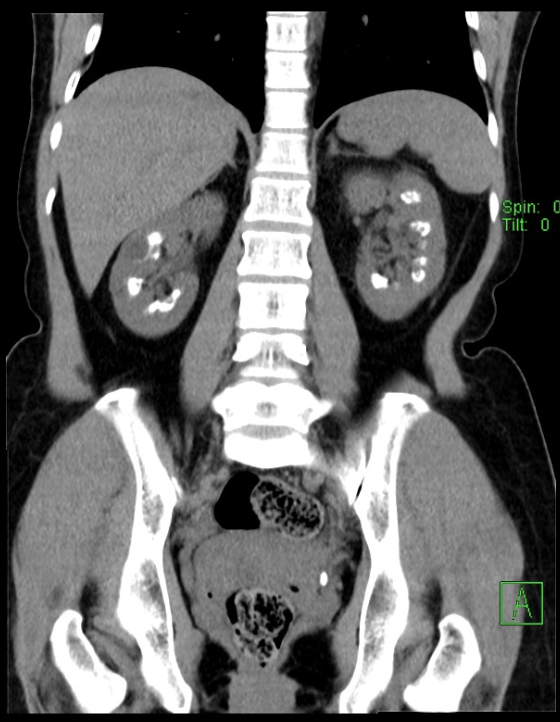

A

Cortical nephrocalcinosis (sequela of cortical necrosis)

Note: Cortical calcifications. Disseminated PCP and tuberculosis can look like this also.

Differential for cortical nephrocalcinosis

Acute drop I blood pressure:

• Shock

• Postpartum

• Burn patients